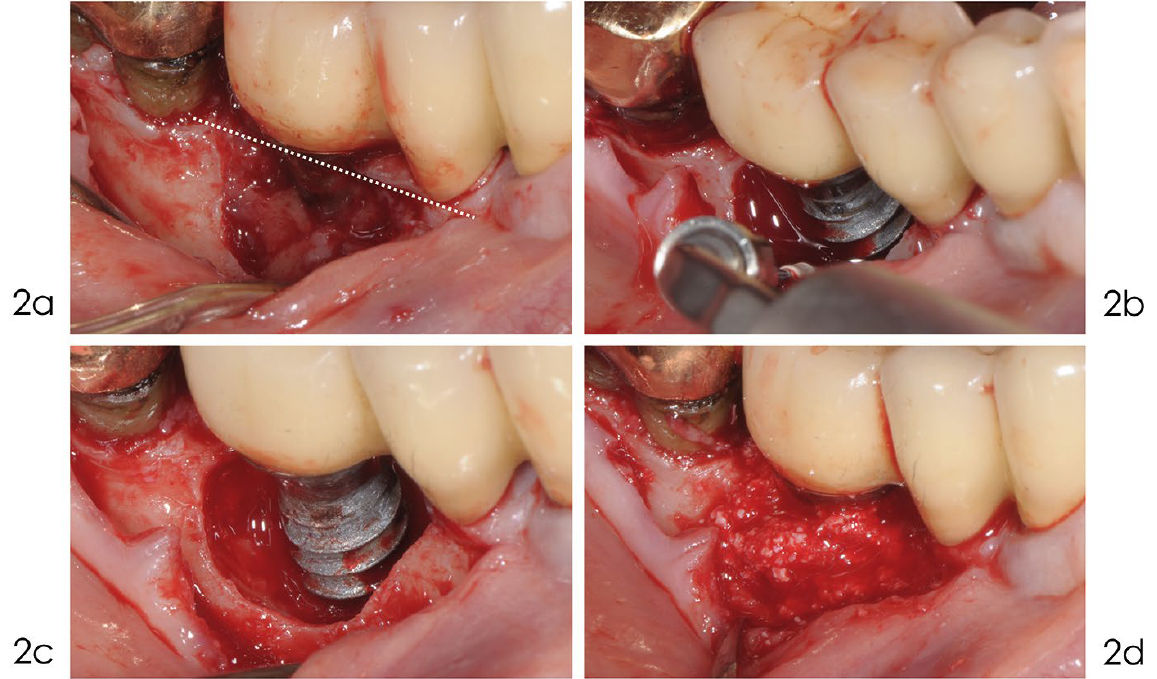

Фото 2a-d. Реконструктивное лечение периимплантита

a) Выполнен линейный разрез по гребню альвеолярного отростка с сохранением мезиального сосочка для облегчения стабилизации лоскута над областью трансплантата. b) Открытая поверхность имплантата была тщательно очищена с помощью ультразвука с тефлоновой насадкой под постоянным орошением физиологическим раствором. c) После удаления грануляционной ткани поверхность имплантата была деконтаминирована 24% раствором ЭДТА и гелем хлоргексидина 1%. d) Внутрикостный дефект заполнен деминерализованным костным материалом крупного рогатого скота с 10% коллагена